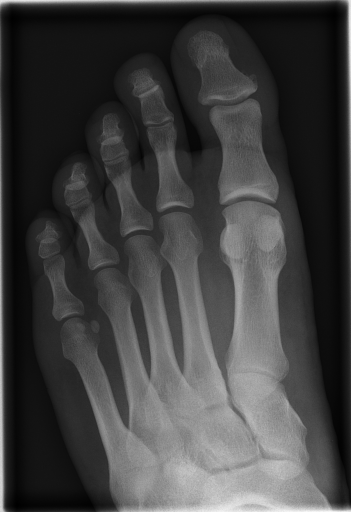

Details of the IRMA database is described in literature [24],[27],[25]. IRMA dataset offers 12,677 images for training and 1,733 images for testing. Figure 4 shows some sample images from the dataset long with their IRMA code in the format TTTT-DDD-AAA-BBB.